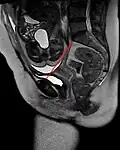

Conjugata vera as measured on sagittal MRI -

Obstetric conjugate, as a measure of the pelvic inlet in the sagittal plane